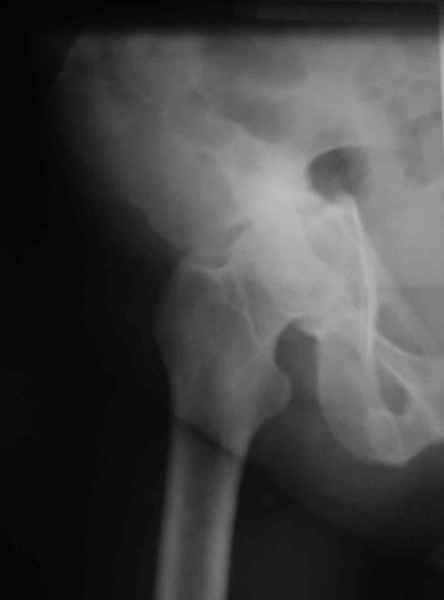

Ув.коллеги, нужен совет по представленному случаю. Пациентка 50лет. В

2003 году в результате дтп получила перелом вертлужной впадины. 1.5

месяца находилась на скелетном вытяжении, в дальнейшем до 10 месяцев

после травмы ходила без опоры на конечность. Вернулась к труду, но в

2006 году перешла на инвалидность и была поставлена в областную

очередь эндопротезирования. В данный момент уже находится в

отделении, но, судя по рентгенограммам и данным КТ, сращения на

уровне перелома не произошло. Что предпочесть?

Вложение не в текстовом формате было извлечено…

Имя     : подвздошн.jpg

Тип     : image/jpeg

Размер  : 12831 байтов

Описание: отсутствует

Url     : http://weborto.net:8080/pipermail/ortho/attachments/20090324/8863a2fd/attachment-0010.jpg